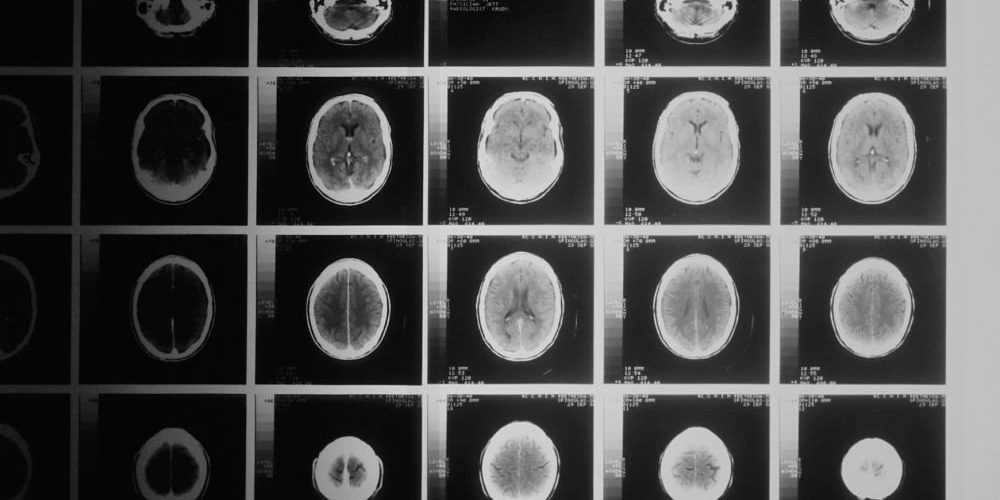

Стероиды способны изменить форму мозга

Исследователи из Нидерландов в ходе изучения мозга почти 25 000 человек пришли к интересному выводу. Форма мозга у употреблявших стероиды и не употреблявших их была различной.

Пациентам с астмой, артритом и экземой регулярно назначают препараты на основе стероидов. Их побочные эффекты хорошо известны, обычно они включают в себя тревожность, перепады настроения и депрессию. Однако учёные из Лейденского университета в Нидерландах обнаружили, что эти препараты, возможно, способны изменить структуру мозга, что подтвердило сканирование этого органа почти у 25 000 человек. Принимавшие глюкокортикоиды пациенты имели меньшее количество белого вещества — ткани, которая соединяет области мозга.

Нидерландские учёные полагают, что их открытие может объяснить связь этих препаратов с неврологическими проблемами. Хотя это и никогда не было доказано учёными, существует широко распространённое мнение о том, что некоторые калечащие неврологические симптомы вызываются стероидами. Новые исследования не доказало окончательной вины лекарств, однако выявило потенциальный механизм.

Вероятно, глюкокортикоиды вызывают изменения в головном мозге, но для подтверждения этих результатов необходимы дополнительные исследования. Глюкокортикоиды — это класс стероидов, которые используются для лечения астмы, артрита и экземы. Они эффективно уменьшает уровень воспалений и подавляют иммунную систему, но связаны с серьезными побочными эффектами, вроде гипертонии, диабета и ослабления костей.